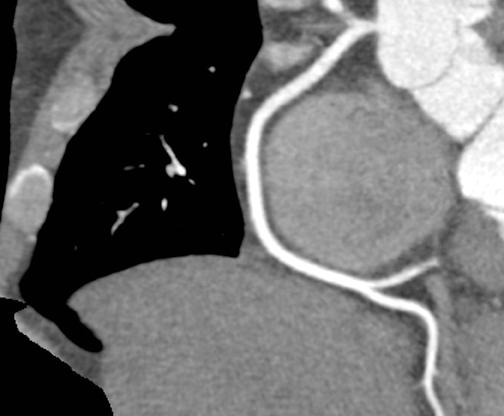

This image from an iCT scanner was done to evaluate coronary artery disease. The scan parameters were: 100 kVp, 50 mAs, CTDI vol 6.3 mGy, DLP 68.3 mGy x cm, iDose4 level = 3, effective dose 0.9 mSv. More images are below.

Logan described how image noise is an important determinant of image quality. It is inversely related to the X-ray beam energy. “Although a reduction in tube current and tube current voltage causes a resultant decrease in radiation dose,” he said, “this also increases image noise, which may compromise image quality.”

Because iDose4 significantly improves spatial resolution and preserves the “natural” appearance of images, image quality improvements are achieved.

“We experimented with low-dose/low-energy scans in the past with suboptimal image quality. Therefore, the dose vs. image quality was not beneficial,” Dean Blair RT(R)(CT), supervisor of the CT department at SOMC said. “Then we installed the iCT with iDose4. Now, our results show an increase in image quality at low dose.”

In addition to the low-energy, low-dose benefits SOMC has experienced, Blair also noted that SOMC has been able to use low injected contrast imaging as a result of the fast scan times and rotation speeds of the iCT.